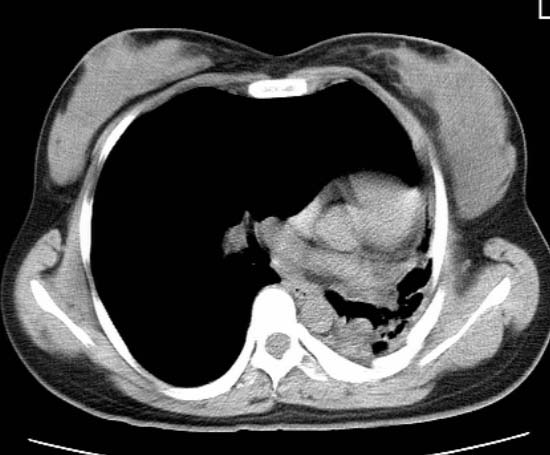

标题: CT25648:求教:是肺发育不全还是结核?

女  20岁。一月前咳血,诊“肺结核”抗痨治疗一月后,咳血停止,现复查。病人精神好。前后ct片对比未见明显变化。既往体检“正常”

1)考虑左肺结核并肺不张、支气管扩张。2)纵隔疝。

以前体检正常只能考虑左肺结核并肺不张、支气管扩张。2)纵隔疝。

考虑左肺结核,左肺毁损,纵膈左偏,既往体检正常不可靠,tb一个月也不会这个样子的,有钙化,应该病程较长,冰冻三尺非一日之寒!

左肺发育不全。

考虑左肺结核,左肺毁损,纵膈左偏,既往体检正常不可靠,tb一个月也不会这个样子的,有钙化,应该病程较长,冰冻三尺非一日之寒

结核,左肺毁损。